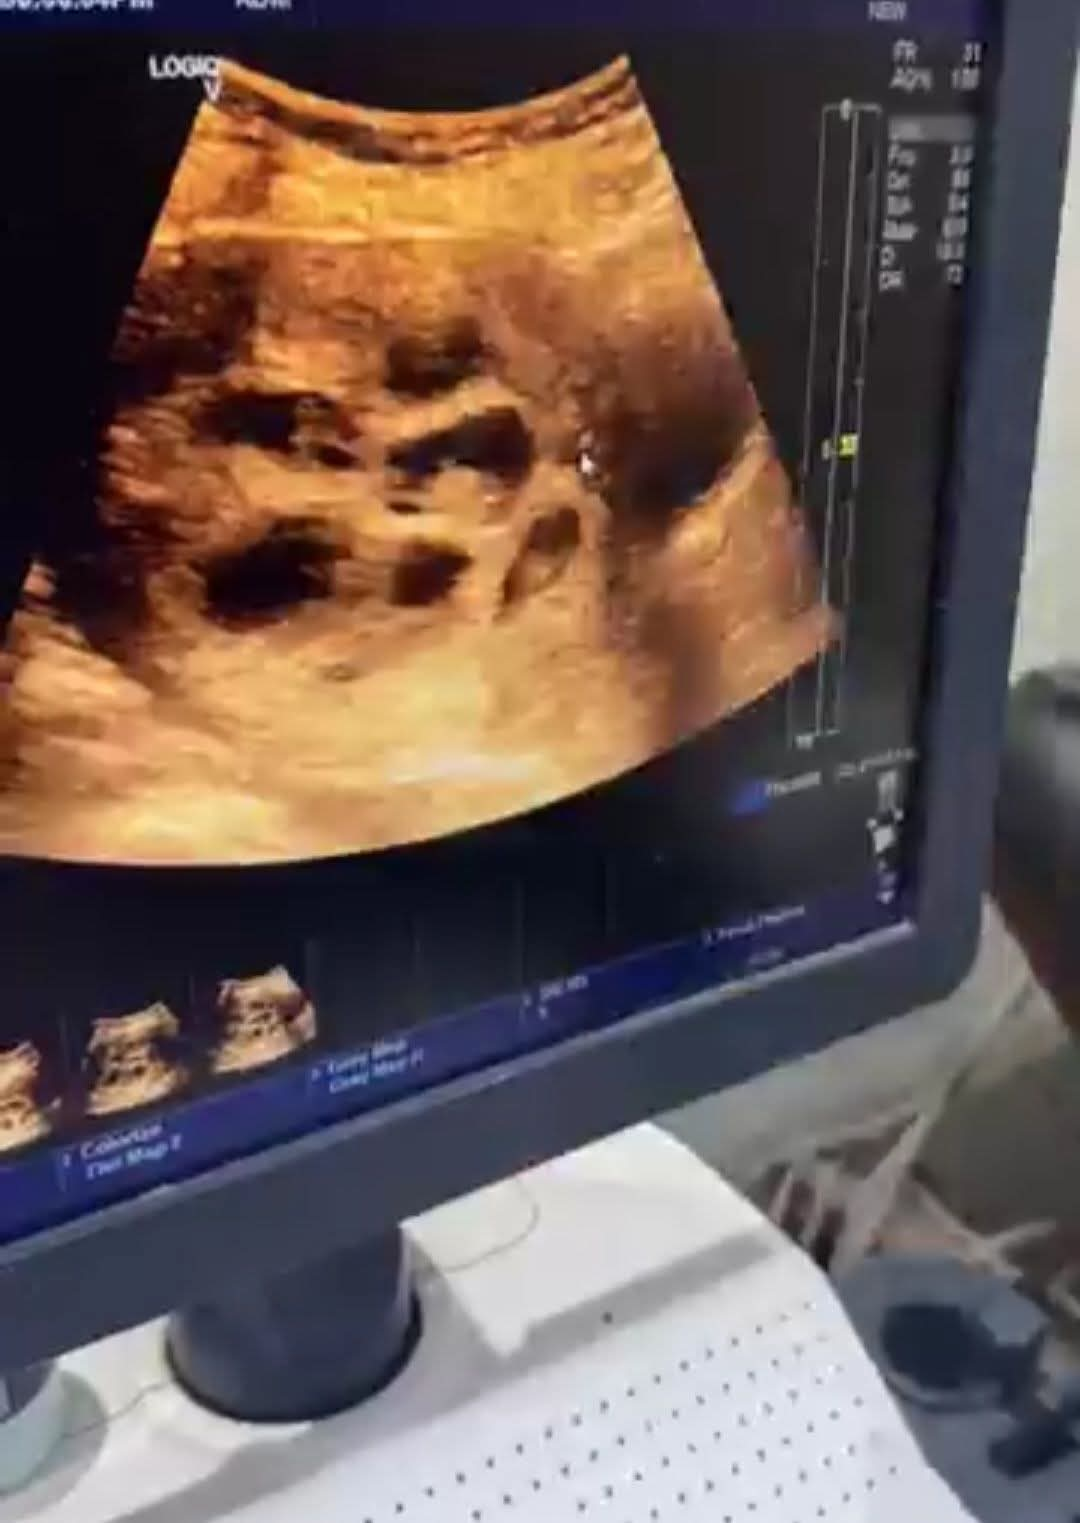

وتداولت عدة صفحات على منصات التواصل مقطع فيديو يوثق لحظة الكشف الطبي على السيدة، حيث يظهر جهاز السونار موضحًا وجود ثمانية أجنة داخل الرحم، بينما يشرح الطبيب المتابع تفاصيل الحالة.